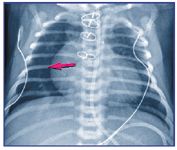

Extra-alveolar air

The presence of extra-alveolar air results from a pressure gradient created by increased intra-alveolar pressure and subsequent rupture of alveoli. Ultimately, air dissects into the perivascular spaces.4 This process may lead to a pneumothorax, pneumomediastinum, or pulmonary interstitial emphysema. The premature neonate is at particular risk because of noncompliant lungs. Diseased or hypoplastic lungs, or lungs subjected to barotrauma from assisted ventilation, are prone to alveolar rupture. A pneumothorax also may occur spontaneously when an infant attempts to overcome tracheobronchial obstruction.2

Air in the pleural space may be under tension, causing a contralateral shift of the mediastinal structures or hemidiaphragmatic inversion on the affected side. In the ventilated neonate, a pneumothorax is assumed to be under tension and almost always requires intervention.5